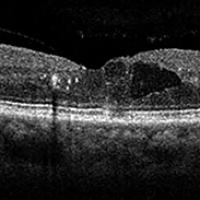

OCT image of a retina

New biomarkers may detect early eye changes that can lead to diabetes-related blindness

New biomarkers found in the eyes could unlock the key to helping manage diabetic retinopathy, and perhaps even diabetes, according to new research conducted at the Indiana University School of Optometry.